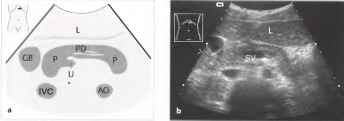

При ультразвуковом исследовании поджелудочная железа выявляется в эпигастральной области кпереди от магистральных сосудов (нижняя полая вена (НПВ), аорта) и позвоночного столба. Маркерами расположения и границ поджелудочной железы являются, прежде всего, сосуды брюшной полости — НПВ, аорта, верхние брыжеечные вена и артерия, располагающиеся ниже тела железы, чревный ствол и его ветви, лежащие краниальнее, селезеночные сосуды, проходящие по задненижней поверхности хвоста, и гастродуоденальная артерия. Нижняя лопая вена в положении поперечного и косого сканирования имеет вид эллипсоидной структуры с коротким передне-задним диаметром и выявляется сразу кзади от изображения головки поджелудочной железы. При продольном сканировании вдоль головки железы нижняя полая вена имеет вид трубчатой структуры с тонкими гиперэхогенными стенками, выявляемой в том же месте — вдоль задней поверхности головки.

В норме поджелудочная железа имеет однородную мелкозернистую внутреннюю эхо-структуру. Она может быть изоэхогенной или несколько гиперэхогенной по сравнению с печенью. В норме на продольных или поперечных сечениях не выявляется каких-либо существенных различий между эхогенностью поджелудочной железы и печени. Нередко поджелудочная железа обладает повышенной эхогенностью, в частности у пожилых людей и лиц, страдающих сахарным диабетом (липоматоз) Это усиливает контраст между поджелудочной железой и гипоэхогенной селезеночной веной. Общими для всех возрастных групп признаками являются ровность и отчетливость контуров, однородность структуры, равномерность распределения эхогенности, четкое разграничение отделов и внутренних структур железы, что, впрочем, не всегда возможно на некоторых группах ультразвуковых приборов, или при недостаточно хорошей подготовке пациента. Ровность контуров железы может иметь некоторые вариации — важное значение имеет четкость отграничения железы от окружающих тканей. Размеры неизмененной поджелудочной железы, измеряемые при ультразвуковом исследовании, соответствуют толщине различных отделов органа. Многие исследователи указывают различные значения максимальных размеров железы, а ряд специалистов считает важным не столько определение абсолютных значений размеров, сколько их сопоставление с остальными признаками. Наиболее правильным считается измерение размеров в перпендикулярном направлении по отношению к передней поверхности каждого из отделов. Размеры поджелудочной железы могут колебаться в значительных пределах — головка может иметь толщину от 11 мм до 30 мм (иногда даже до 32 мм), тело — от 4 мм до 21 мм. хвост — от 7 мм до 28 мм (иногда до 35 мм).

Рис.1. а, b На снимке в верхней поперечной плоскости брюшной полости поджелудочная железа имеет вид гипоэхогенного органа, дугообразно изгибающегося над позвоночным столбом, аортой и нижней полой веной; в поджелудочной железе определяется двустенный эхогенный проток. АО - аорта, GB - желчный пузырь, IVC - нижняя полая вена, L - печень, Р - поджелудочная железа, U - крючковидный отросток, SV - селезеночная вена, PD - проток поджелудочной железы.